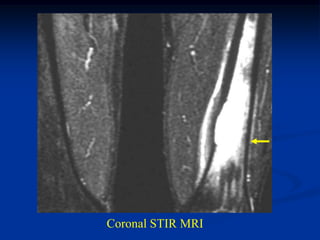

Case #417

17 year male

EG distal femur

Lateral view

Coronal T-1 MRI

Sagittal T-2 MRI

Coronal STIR MRI